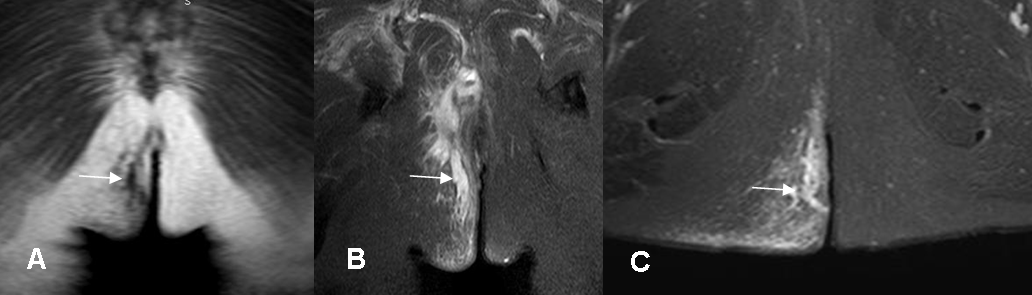

Fig 46 A. Fístula.

A: RM coronal en T1, B: RM coronal en STIR y C: RM axial en STIR. Trayecto de fístula perianal derecha, identificada como imagen serpentiginosa hipointensa en T1 e hiperintensa en STIR, rodeada por cambios inflamatorios en los tejidos blandos.

Fig 46 B. Fístula.

A: RM axial en STIR. Fístula perianal izquierda.

B: Thriveax T1 simple y C: Thriveax T1 con contraste. El trayecto fistuloso realza con el contraste.